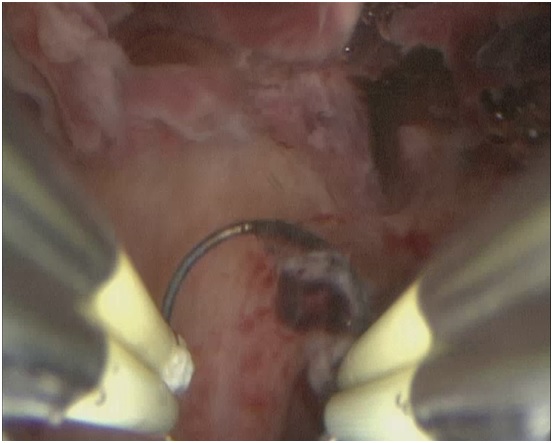

Произведена гистерорезектоскопия под контролем лапароскопии. При гистероскопии сразу за внутренним зевом в области рубца по передней стенке выявлена «ниша» 3,0*2,0*1,0 см, выполненная темными сгустками крови и остатками хориальной ткани (см. рисунок №1). Петлей резектоскопа в биполярном режиме в «нише» удалена патологическая ткань (см рисунок №2). Гистологически подтверждено наличие ворсин хориона, элементов трофобласта.

Рис. 1. Остатки хориальной ткани

Остатки хориальной ткани в области п/о рубца на матке